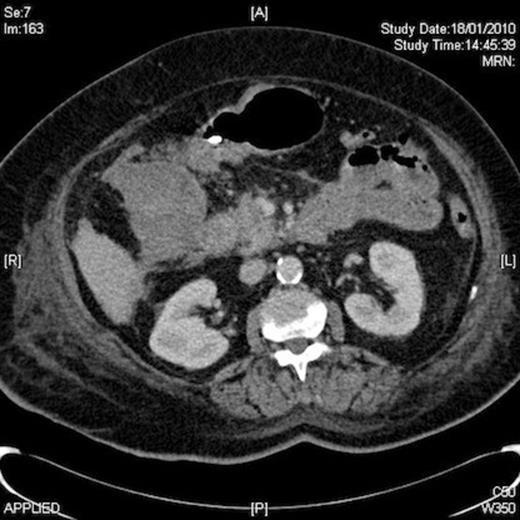

Despite no obvious cause of blood loss her haemoglobin was discovered to be low again at 8.5 gm on day 6 of admission. At this time, she received two more units of blood. An upper G I endoscopy (OGD) was arranged which revealed extensive mucosal oedema, bruising and narrowing of the first and second parts of the duodenum. CT scan of the abdomen was performed, which revealed a 10cm RUQ mass, compressing on and contiguous with 2nd part of duodenum, presumed to be a sizeable haematoma. A small amount of free blood in the peritoneal cavity and pelvis was also noted.

Once the diagnosis of gastric outlet obstruction due to compressing haematoma was established on CT, she received vitamin K and subsequently was managed conservatively under the combined care of the surgeons, haematologist, cardiologist and nutritionists. Her nasogastric tube remained in situ and it kept draining loads of biliary aspirate since her admission.